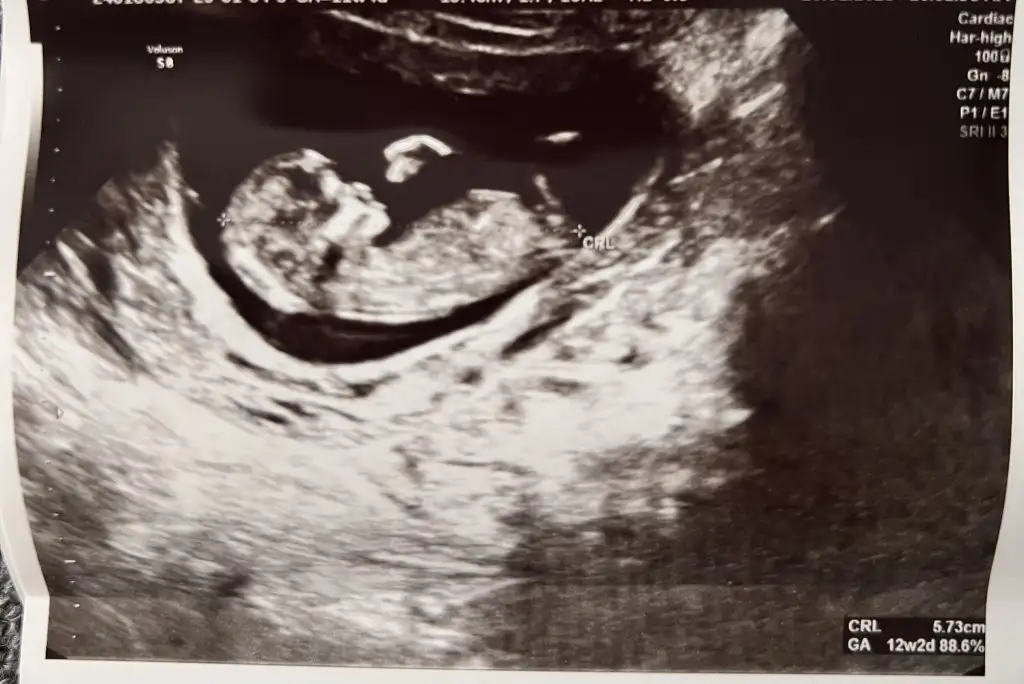

Merhaba kızlar 12 haftalık ultrason görüntüsünden cinsiyet belli olur mu ya ben anlamıyorum :) Doktorumda 14. Haftadan önce cinsiyet söylemiyorum dedi. Yanılma olabilir diye.